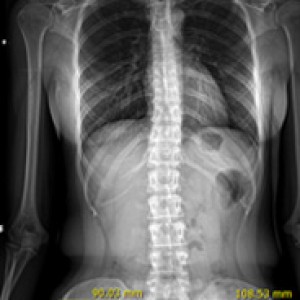

발의 아치가 무너지거나 발목 관절이 틀어지면 연쇄적으로 척추, 골반 불균형과 다리 길이 차이를 유발할 수 있습니다. 연산당당 족부 교정 장치는 이러한 전신의 구조 문제를 개선하기 위해 발의 아치와 발목 관절을 제자리로 교정합니다.

올바른 체형 개선

척추/관절 손상 방지

다리길이 측정

엑스레이 검사